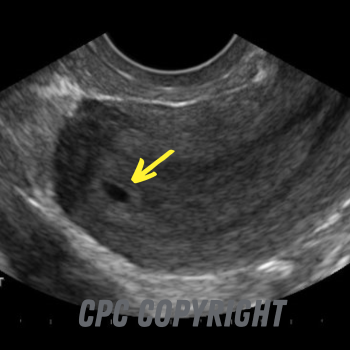

3 weeks after conception

3 weeks after conception (just one week after your missed period) you will see a small sac of fluid called the gestational sac. The sonographer will measure this and be able to tell you how far along you are in the pregnancy. The fetus (baby) at this point is too small to measure.